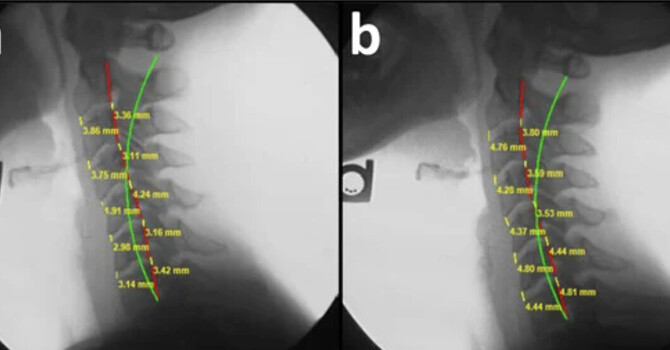

• Radiographic Sagittal Alignment and Kinetic Chain Alterations in Geriatric Patients with Scoliosis: A Case Series